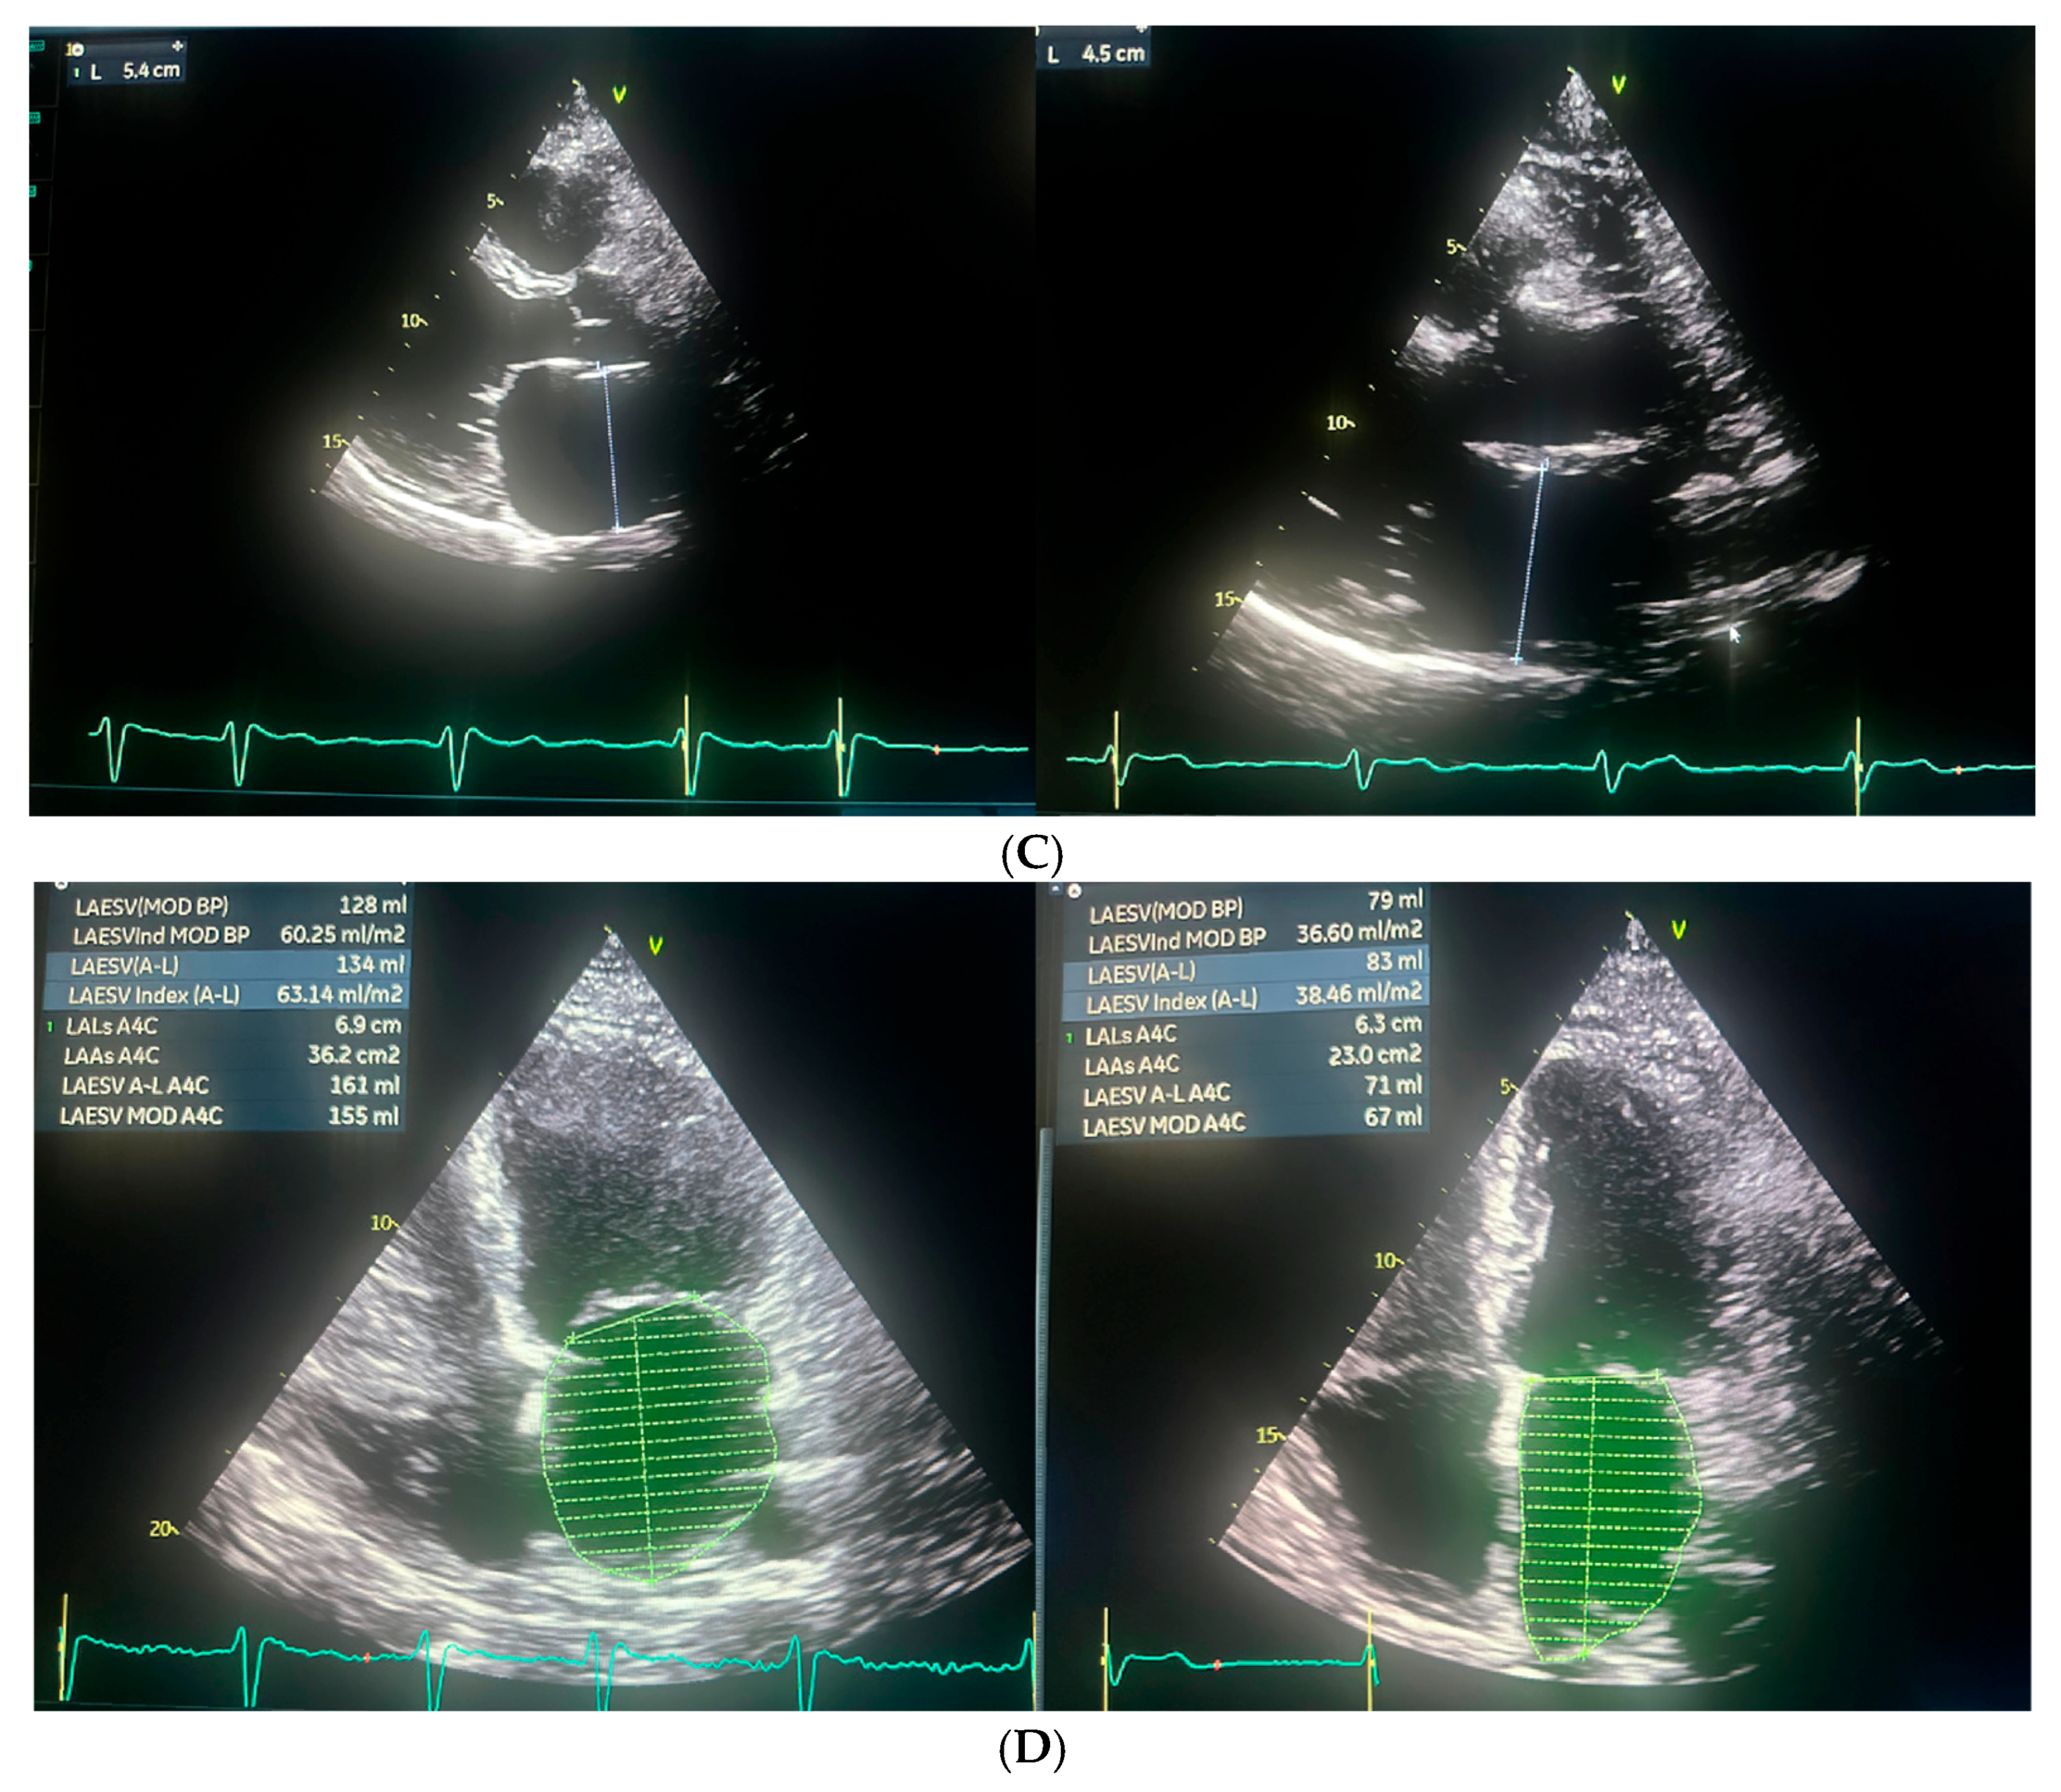

| Echocardiographic Parameters | First Admission | Ablation | Follow-Up |

|---|---|---|---|

| LA (mm) | 48 | 54 | 45 |

| LAA (cm2) | - | 36.2 | 23 |

| LAVI (ml/m2) | - | 60.25 | 36.6 |

| RAA (cm2) | - | 22.8 | 21.5 |

| TAPSE (mm) | - | 18 | 23 |

| PALS (%) | - | 5 | 20 |

| RVSP (mmHg) | 37 | 40 | - |